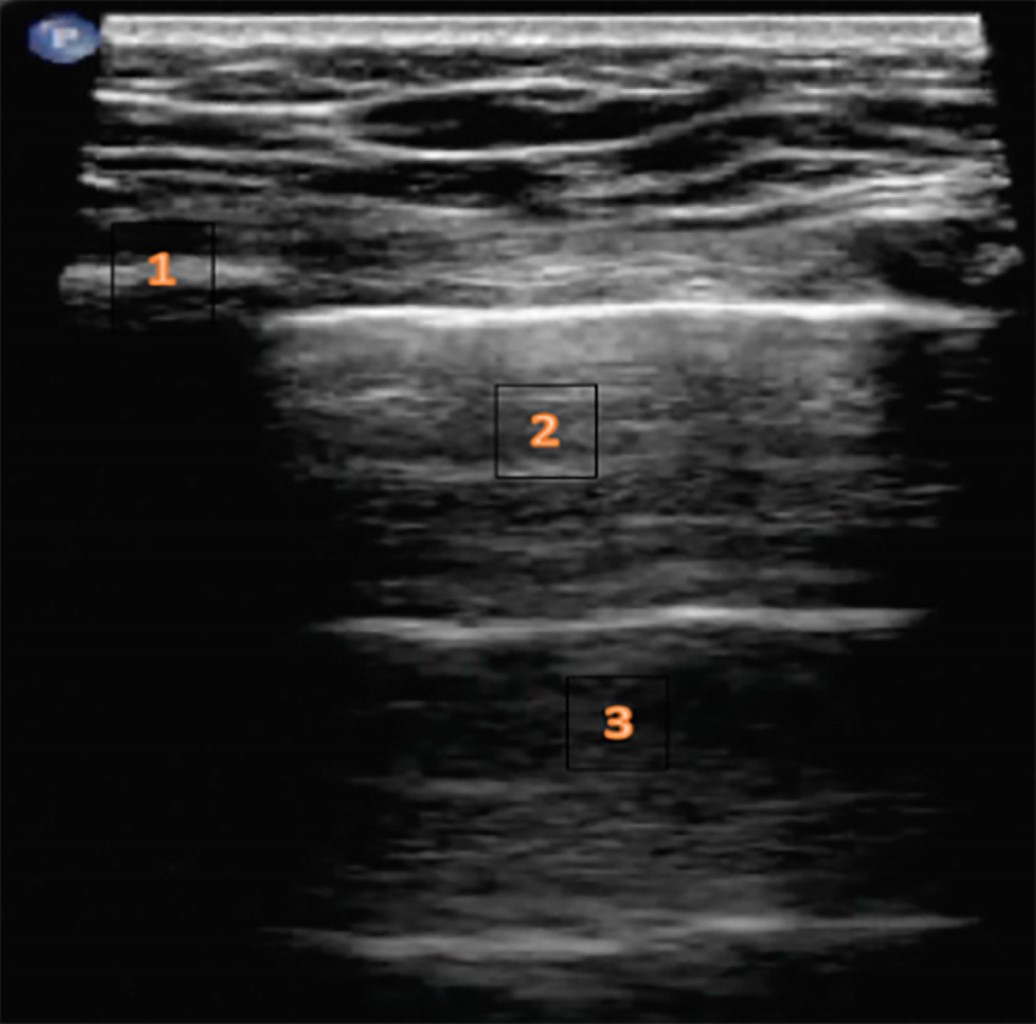

Podemos observar varios signos que son sugestivos de derrame pleural(5,10):

• 1. Signo del cuadrado o del quad (sharp sign): imagen cuadrada que se obtiene en modo B donde el derrame pleural es un área hipo/anecoica limitada por la pleura parietal arriba, la pleura visceral y el pulmón abajo y sendas costillas a los lados.

• 2. Signo de la medusa: pulmón flotando en el líquido por aparición de atelectasias compresivas y colapso pulmonar basal.

• 3. Signo de la pleura desflecada: en una pleura normal ambas hojas están unidas y se comportan como una línea hiperecogénica única. Cuando empieza a acumularse líquido entre ellas empieza a observarse la separación progresiva de ellas.

• 4. Signo del sinusoide (modo M): vamos a ver la pared torácica como líneas paralelas continuas ("agua") y por debajo un área de ecogenicidad variable en función del tipo de derrame. Debajo de esta zona identificamos el pulmón como una zona oscilante en relación con los movimientos respiratorios. Se ha descrito que la aparición de este signo indica la existencia de un derrame con baja viscosidad, permitiendo su drenaje de forma sencilla. Para poder llevar a cabo este drenaje en condiciones de seguridad es importante que exista por lo menos 15 milímetros de distancia en inspiración (Figura 3).